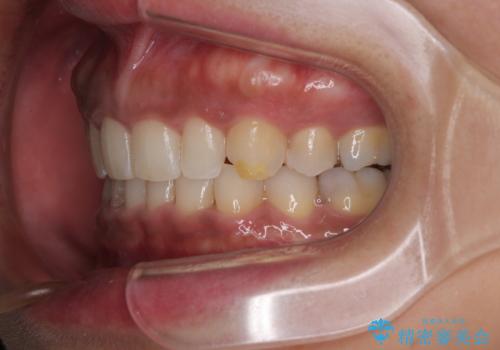

- 下顎前歯部には叢生が認められ、口を自然に閉じにくい状態でした。また、噛み合わせが深い「ディープバイト」の状態で、見た目だけでなく将来的な奥歯への負担も懸念されました。

口元の突出感を改善するため、上下左右の小臼歯4本を抜歯する矯正治療を計画しました。

「矯正装置が目立つのは避けたい」というご希望があったため、プラスチックブラケット+コーティングワイヤーを使用した審美装置を選択しました。